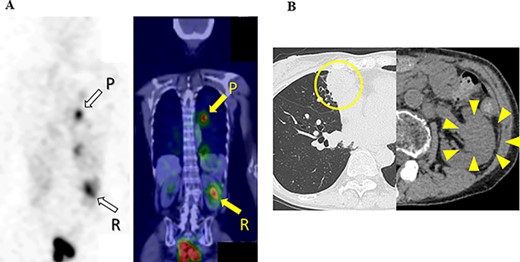

Ten months after the start of lenvatinib, CT showed a decrease in the sizes of pulmonary metastases (Fig. 3A) and renal metastasis (Fig. 3B) (tumor reduction rate: 45%). Remnant thyroid resection was performed and followed by RAI therapy with 100 mCi. In 131I scintigraphy, some lung metastases showed radioiodine uptake, whereas others did not. Radioiodine uptake was also observed in the left renal tumor, but not in the right kidney (Fig. 4A); therefore, the left renal tumor was finally confirmed as renal metastasis of PTC. Since the sizes of pulmonary and renal metastases both increased after the RAI therapy (tumor growth rate: 71%) (Fig. 4B), the administration of lenvatinib was resumed from a dose of 4 mg/day. After resuming lenvatinib, she has been in SD status for 6 months.

131I scintigraphy and CT images of the chest and abdomen after the second surgery; (A) in 131I scintigraphy, some lung metastases showed radioiodine uptake, whereas others did not. Radioiodine uptake was also observed in the left renal tumor, but not in the right kidney; left: RAI scintigraphy, right: SPECT–CT, P: pulmonary metastases, R: renal metastasis; (B) pulmonary and renal metastases both increased in size.